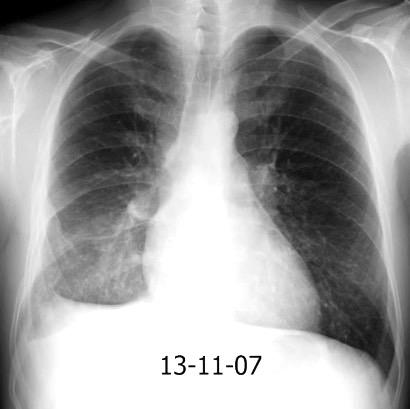

Neumonía a neumococos base izda. con derrame que aumenta.

Broncograma en lateral y en US.

(36-66% en ingresados)